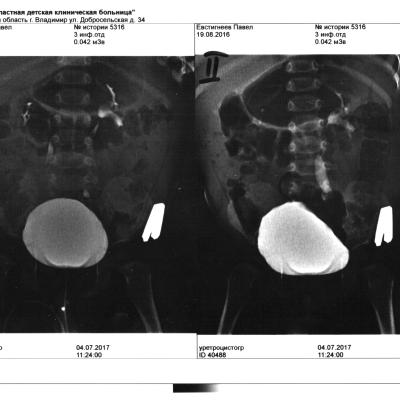

Сыну 1 год, постоянные пиелонефриты с 6 месяцев. Месяц назад обследовались в областной больнице г. Владимира. Диагноз:двухсторонний ПМР 2-3 степени, клапан задней уретры?. Клапан не могут посмотреть,нет оборудования. Пока носим катетер Фалея, но постоянно подскакивает температура под 40.

Прилагаю цистографию.